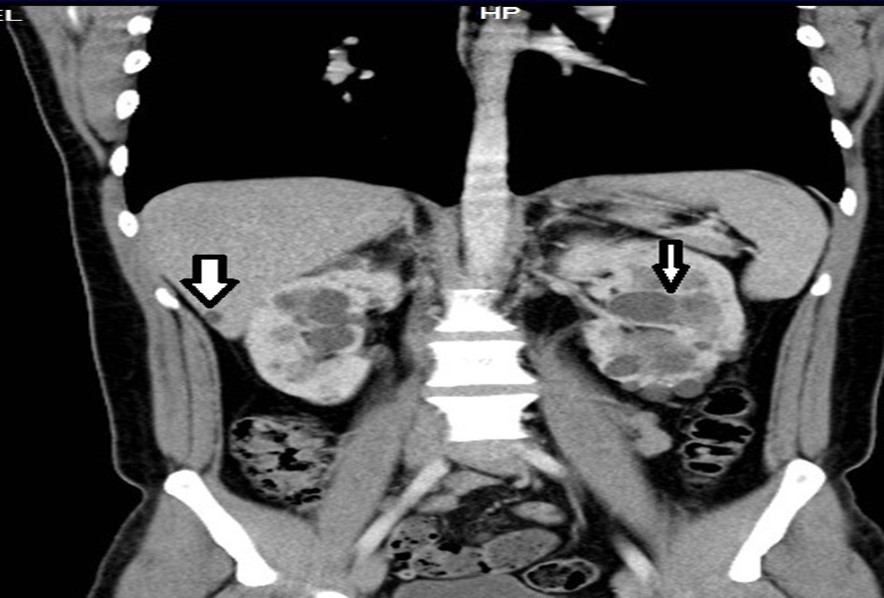

33-year-old male, son of the woman from case 1, with diagnosis of polycystic kidney and liver disease (Figure 3, Figure 4) since 29 years old , with normal liver and kidney function; At that moment general measures were started based on a diet low in sodium, increasing the consumption of natural liquids, avoiding nephrotoxic drugs and monitoring blood pressure.

At physical examination, without alterations. The abdominal thomography reports kidneys in habitual anatomical projection with loss of their morphology and increased sizes with loss of the sinus parenchyma relationship due to cystic-looking structures; right kidney with dimensions 14.3x 8.9 x 6.6 cm left kidney 17.3 x 11.6 x 8.2 cm in its longitudinal, transverse and anteroposterior diameters respectively, poorly determined echogenic renal sinuses, the left renal sinus with solid oval shades measuring 0.6 to 0.8cm on average and some calcifications; liver ultrasound showed cystic lesions. Laboratory creatinine 0.96mg/dl, urea 31.03 mg/dl

Figure 3.Contrast CT coronal reconstruction shows small liver cysts, kidneys are enlarged by multiple cysts.